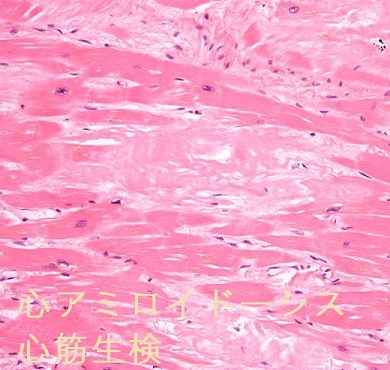

- 心アミロイドーシス;心臓の間質にアミロイド線維が沈着する二次性心筋症で不整脈・心肥大・左室拡張障害による心不全。心電図で低電位差、心エコーで心筋肥厚・エコー輝度増加、心筋生検が診断に有用。

甲状腺アミロイドーシスによる甲状腺機能低下症に心アミロイドーシスを合併すれば、徐脈・心不全が相乗効果で増悪します。心アミロイドーシスの生命予後は4カ月です。

甲状腺アミロイドーシスの細胞診では通常、写真のように無構造好酸性物質を認め、その中に線維芽細胞が増生しています。濾胞組織は破壊され、細胞成分は少ない。

甲状腺アミロイドーシスの組織診